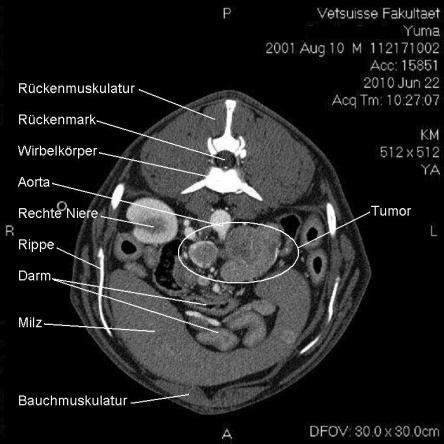

Die Computertomographie (CT) liefert mittels eines röntgenähnlichen Verfahrens ein dreidimensionales Bild des untersuchten Körperteils. Da das untersuchte Tier vollständig ruhig liegen muss, wird Yuma zur Untersuchung narkotisiert.

Im CT wird ersichtlich, dass sich der Tumor, welcher von der linken Nebenniere ausgeht, schon sehr weit in das Gefässystem von Yuma vorgearbeitet hat. Krebsausläufer finden sich wie erwartet in der Hohlvene, aber auch in der Nierenvene sowie in einer weiteren grossen Vene. Der Geschwulst ist somit inoperabel.